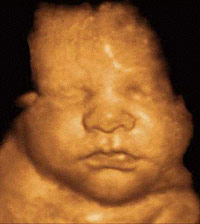

• La ecografía: Es la más usada. Entrega imágenes a través de ultrasonidos. Permite evaluar la anatomía en detalle y el crecimiento del niño. Sirve para analizar marcadores que se asocian a alteraciones de los cromosomas.